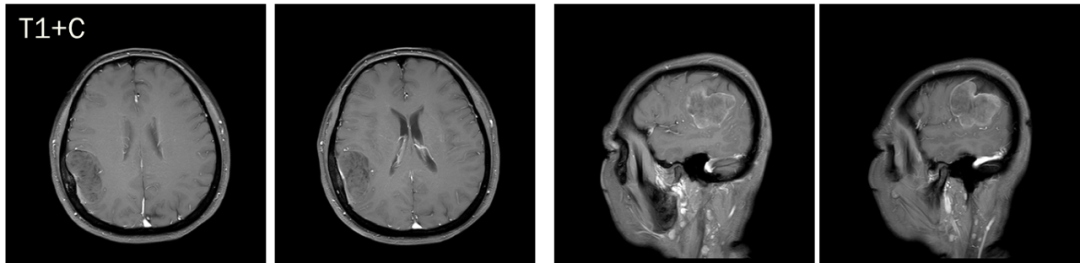

CASE 4

男,62 岁

右侧顶叶区混杂信号占位,T1、T2 内部条样低信号影,血管留空信号;增强可见明显强化,内部信号欠均匀,内见强化迂曲血管影。

诊断:右侧顶叶区血管外皮瘤